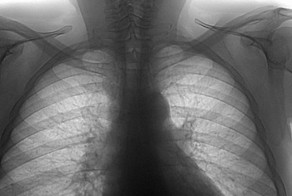

Жительница одной из деревень Бангладеша Хосинеара Бегум уже много лет страдает от невыносимых мучений - ее лицо и тело покрыты гроздьями опухолей, некоторые из которых достигают размера крупной картофелины. Соседи называют ее картофельной женщиной, пугают ею маленьких детей и при встрече переходят на другую сторону улицы. Однако она не всегда была такой.

Когда Хосинеара родилась, у нее было только несколько небольших шишек на лице и шее и образование на верхней губе, но местный врач его удалил. В 16 лет ее выдали замуж, они с мужем очень друг друга любили и через год у них родился сын.

Но вскоре после рождения сына болезнь начала прогрессировать. Образования появились по всему телу и стали увеличиваться.

"Эти опухоли болят и ужасно чешутся, иногда я расчесываю их до крови. Я больше не могу выносить эту боль. Со мной никто не разговаривает и не общается. Едва завидев меня на улице, люди разворачиваются и идут в другую сторону. Дети меня боятся. Даже мой трехлетний внук плачет при виде меня. Я живу как изгой. Думаю, что единственный выход для меня - это умереть", - говорит Хосинеара.

Она не может нормально говорить, есть, носить обычную одежду. Каждое движение сопровождается дикой болью. Женщина в таком отчаянии, что целыми днями плачет и молит бога о смерти.